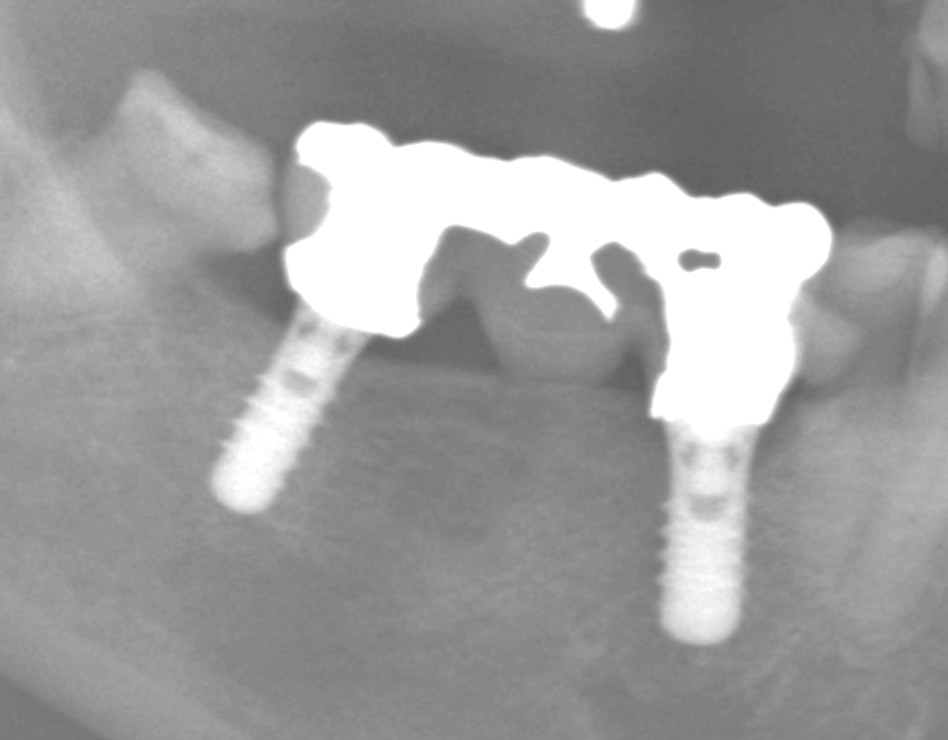

インプラントは、埋め込まれたフィクスチャー(本体)の上にアバットメントや被せ物(上部構造)が装着されています。

この上部構造は、特殊なドライバーを用いて着脱する構造になっており、メーカーが異なっても互換性のあるドライバーが存在する場合があります。

そのため、「メーカーが不明」でも、互換ドライバーを使用して取り外しや調整を行えることも少なくありません。